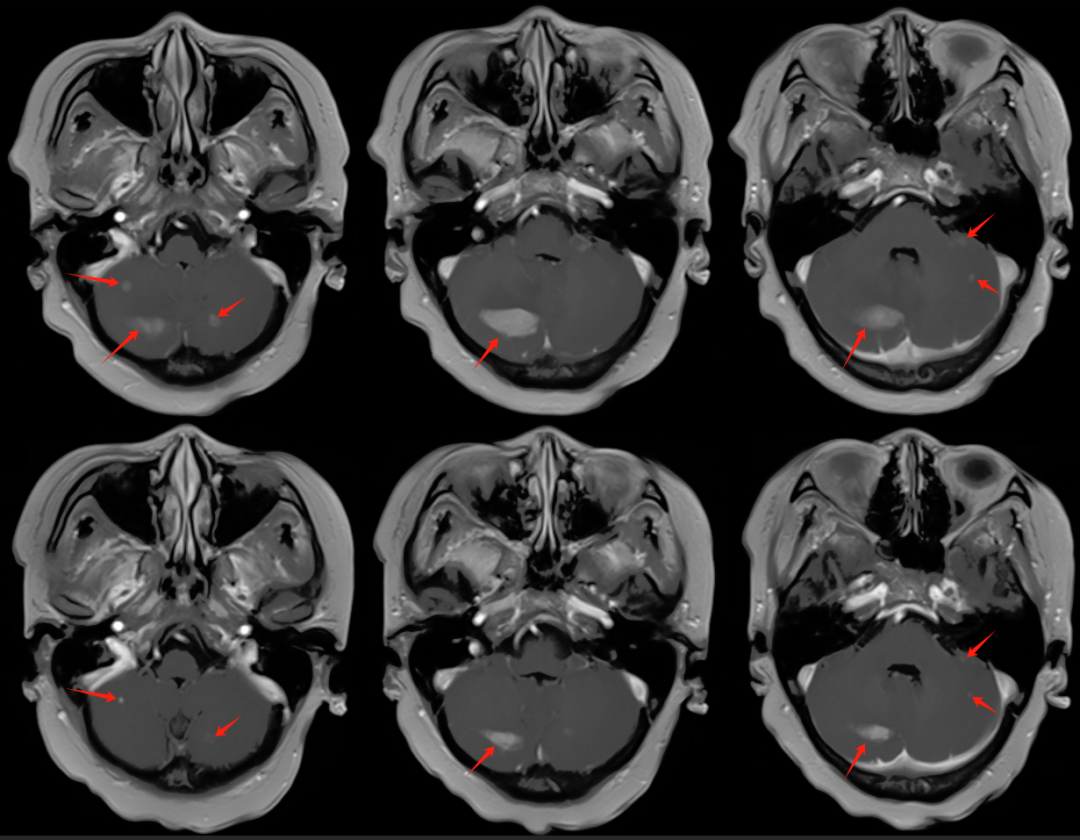

【學科風采】乳腺癌患者千里求醫(yī),成功治療多發(fā)腦轉移瘤、脊髓轉移、腦膜轉移、椎管內多發(fā)轉移結節(jié)、肺炎及肺門轉移患者